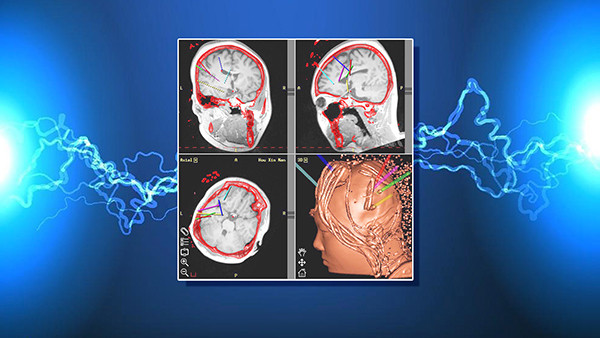

张主任强调,常见的发呆、忘事、无目的无意识的四处溜达,都有可能是大脑异常放电的表现,只是经常被您忽视了。而一旦您错过了这些蛛丝马迹,当“大脑电网”崩塌的时候,最严重的后果就是癫痫。张主任还介绍,食物是癫痫的一个主要诱发因素,除了食物意外,癫痫还有哪些诱发因素呢?节目现场,张主任带来了目前最尖端的脑电波监测设备,我们通过脑电波监测就可以早期发现大脑异常放电,避免危险事件的进一步发生。脑电波是如何检查的呢?让我们一探究竟。